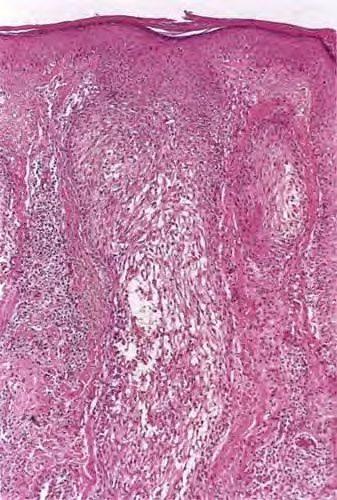

In 1957, Pinkus described alopecia mucinosa, the term used when follicular mucinosis affects terminal hairbearing areas and is associated with hair loss . Papules and plaques may be present or inconspicuous in this form, which may show only alopecia. Scarring is seen more commonly when alopecia mucinosa is associated with cutaneous T-cell lymphoma. Others claim that alopecia mucinosa is simply one of the many morphologic variants of mycosis fungoides , whereas LeBoit and LeBoit acknowledged the paradoxes of alopecia mucinosa that have led to the debate over classification (. Histopathology. Within the outer root sheath and sebaceous gland epithelium, there is reticular epithelial degeneration that sometimes evolves into more extensive cavitation within which mucin is deposited . Occasionally, little mucin can be detected, perhaps because of removal of this water-soluble material in the processing procedure. The deposited mucin is an acid mucopolysaccharide that stains metachromatically with toluidine blue at pH 3.0, as well as with Alcian blue at acid pH. The fact that it can be substantially removed by digestion with hyaluronidase demonstrates that the mucin is predominantly hyaluronic acid. Colloidal iron stain may also be used for its detection. |

Inflammation is composed of lymphocytes and histiocytes, but there can also be eosinophils. There may be exocytosis into the outer root sheath epithelium of the infundibulum and the sebaceous gland epithelium. Although individual pathologic criteria are not absolutely diagnostic of the type of |

follicular mucinosis (primary or secondary), features that have been proposed as favoring a lymphoma-associated lesion include an atypical lymphocytic infiltrate or increased density of the perifollicular infiltrate with substantial folliculotropism . This study also suggested that a prominent eosinophilic infiltrate and more substantial mucin deposition tend to favor a benign process, but a subsequent study failed to substantiate these findings . |